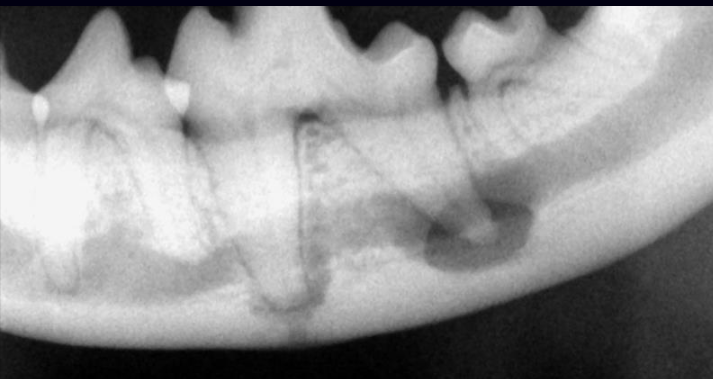

22

Q

DX?

A

ostéomyélite

=> pas une lx endodontique comme telle, mais peut en être une conséquence dans les cas chroniques très sévères